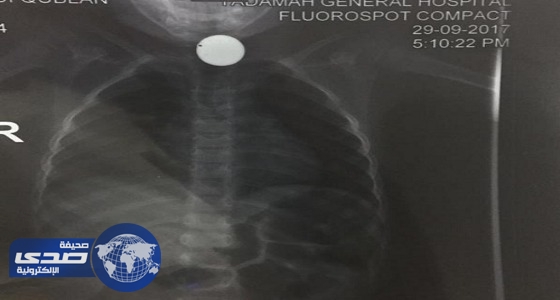

تفاصيل انقاذ حياة طفل في الخفجي ابتلع قطعة معدنية